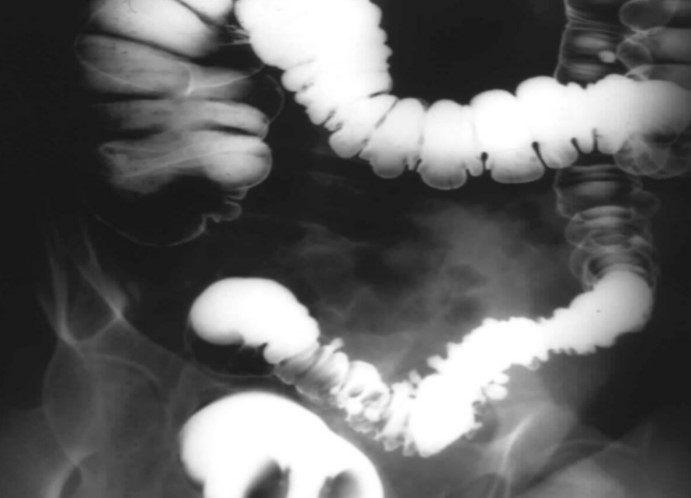

What does this X ray show?

Diverticular disease